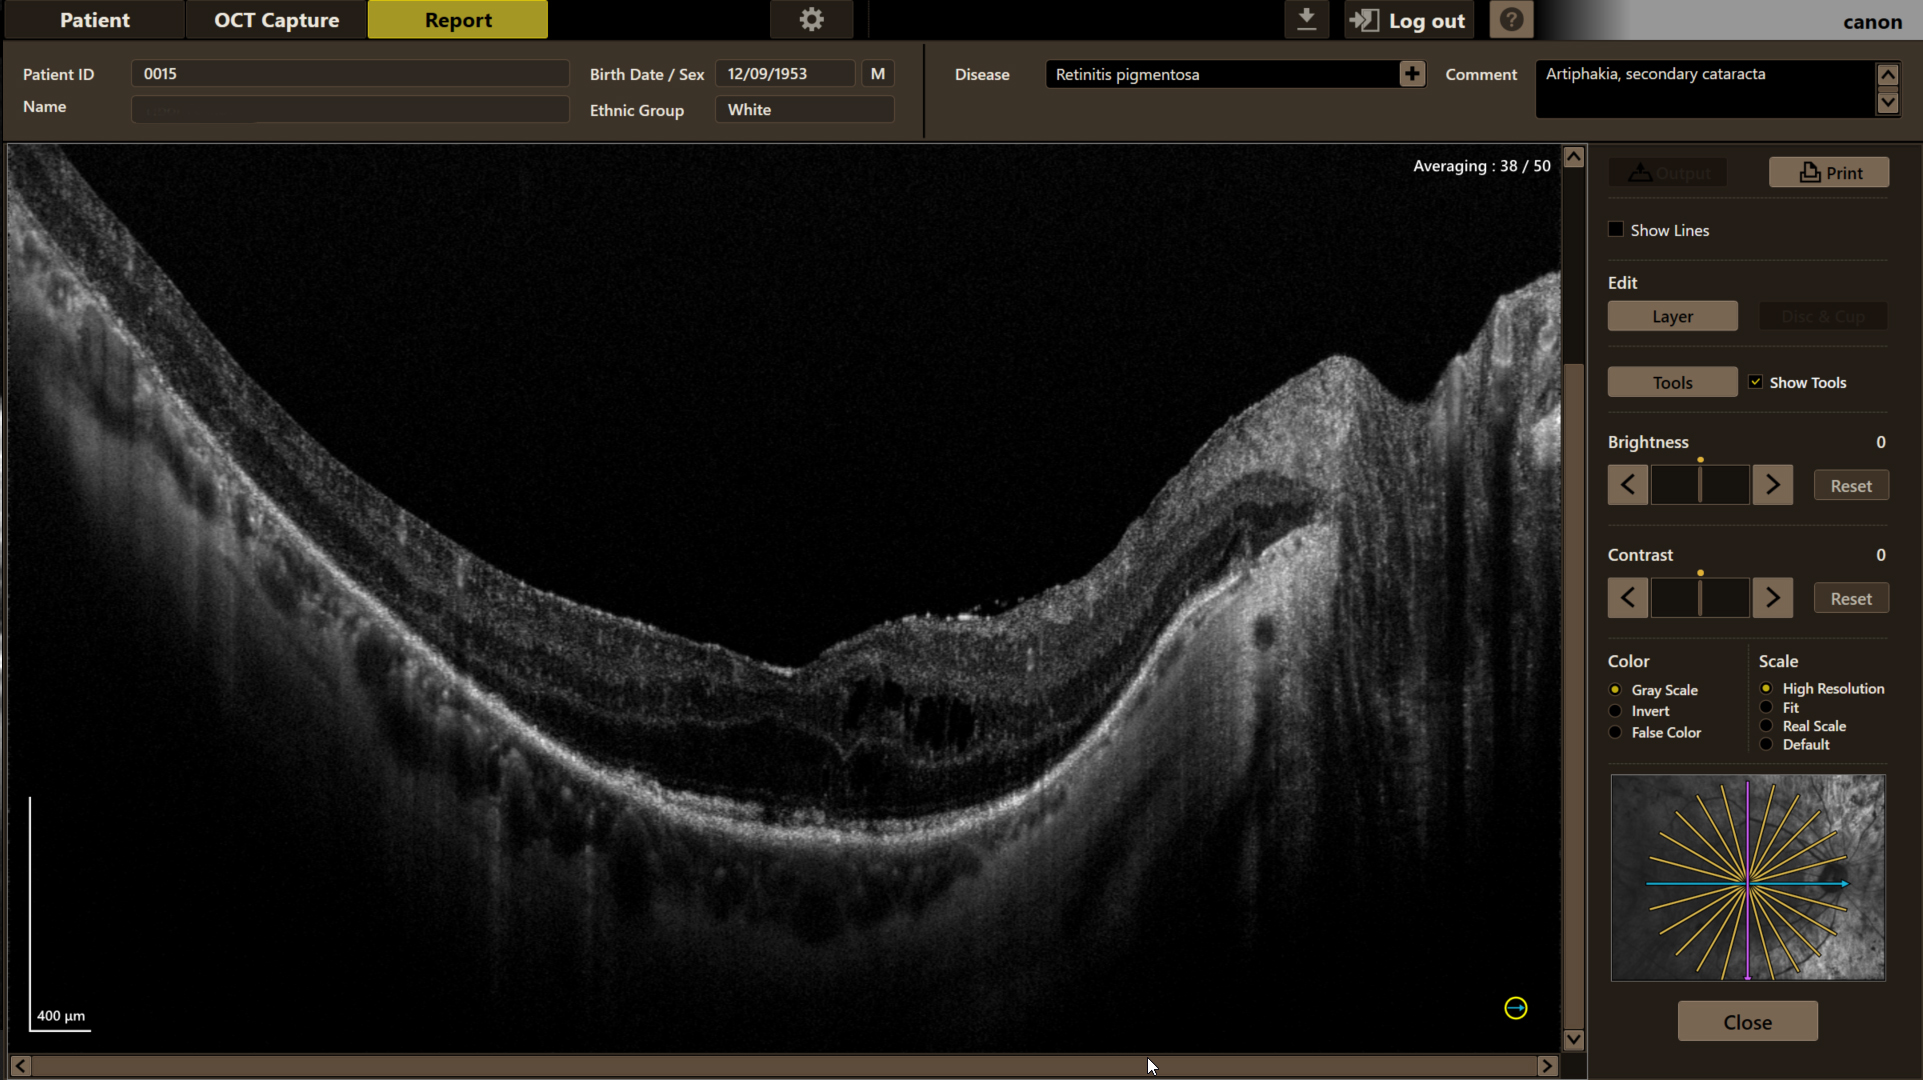

Пігментний ретиніт (пацієнт з артифакією) зображення отримане за допомогою оптичного-когерентного томографа Canon Xephilio OCT A1 (псевдоколір, High Definition)

Пігментний ретиніт (пацієнт з артифакією) зображення отримане за допомогою оптичного-когерентного томографа Canon Xephilio OCT A1 (шкала сірого, High Definition)